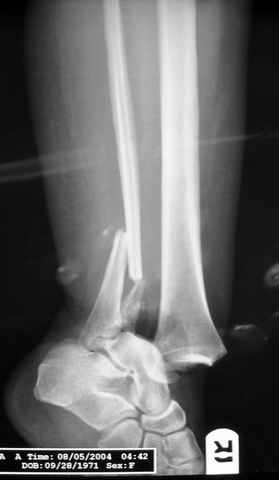

Re: ANKLE FRACTURE

Я вот все в толк не возьму смысл отдельной фиксации малоберцовой кости пластинкой, если все равно будет аппарат с фиксацией стопы, т.е. возможностью провести спицы в пятку, таран, наружную лодыжку и еще черт-те куда. Остеосинтез пластинкой выглядит логичным в случае, когда наружная фиксация планируется как временная. Но тут-то аппарат будет окончательным фиксатором.

I can't realize why plate fibula separately if anyway external fixator including the foot is planned, i.e. one may insert wires to the talus, calcaneus, lateral malleolus and anywhere else. Plating looks reasonable if only temporary ex-fix is planned, but in the case it will be definitive.

As I mentioned before (down), in Dr. Salvi's case, I am for temporary fixation, sparing even the talus (not to get wire as possible vehicle for contamination) and than early fusion.

Fixing the fibula, will provide some stability to the ankle and through the incision relatively far from the major zone of injury (antero-medial), and if we do want to restore the anatomy (if feasible), that is the first step - as T. Rüedi told us a long time ago.